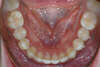

Traitement par gouttières et chirurgie

Fin de traitement